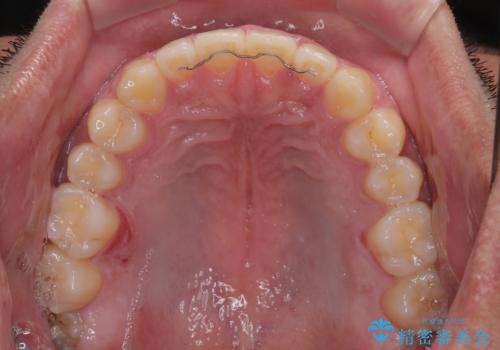

舌のトレーニングをしっかりと行ってくださったおかげで、順調に治療を終えることができました。

舌の突出癖が速やかに改善され、後戻りによるスペースは今のところ認められておりません。